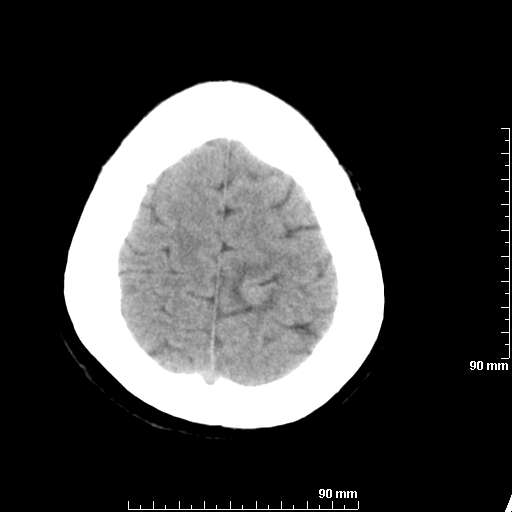

我院西门子单排CT由于一零件受损而产生的伪影.

哈哈,都不是。是虑线器fiter裂损。大家没想到吧。

哦,跟脑出血有点像哦

形状不规则,边缘模糊。比较特殊的一种伪影哈!

这种伪影很常见!伪影应该是在视野的中心的。

西门子的虑线器fiter裂损这才是很难见的问题,GE的最常见

虑线器老化,中间崩裂一块掉了